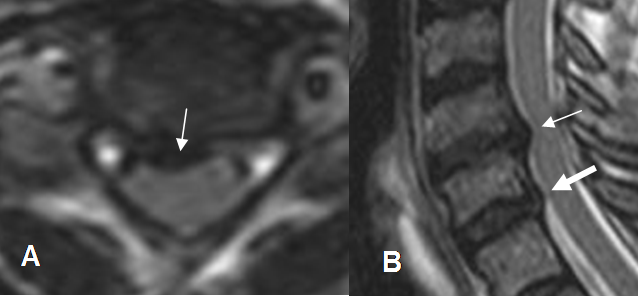

Fig 101. Hernia paramediana.

A: RM sagital y B: RM axial en T2. Prominencia asimétrica paramediana izquierda, que corresponde a hernia. Adicionalmente hay canal estrecho asociado.

Fig 109. Regresión de hernia.

A y B: RM axial en T2. Hernia paramediana derecha. En un control posterior, ha disminuido el tamaño y la compresión de las raíces.

Fig 110. Regresión de hernia.

A y B: RM sagital en T2. Hernia mediana en L3-L4, que después de 7 meses, muestra disminución de su tamaño y menor compresión del saco dural. Cambios degenerativos en las placas terminales de L3-L4 y

L4-L5 y artefactos sobre el cuerpo de L4, ocasionados por materia de fijación posterior. (Puntas de flecha).